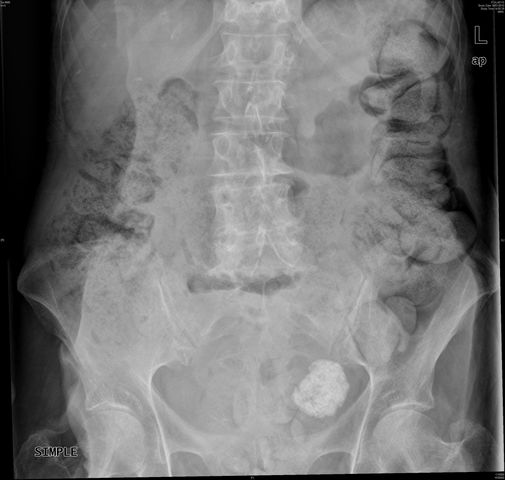

MqO Condensación pulmonar derecha por neo y neumonía añadida. Cálculo coraliforme izquierdo.